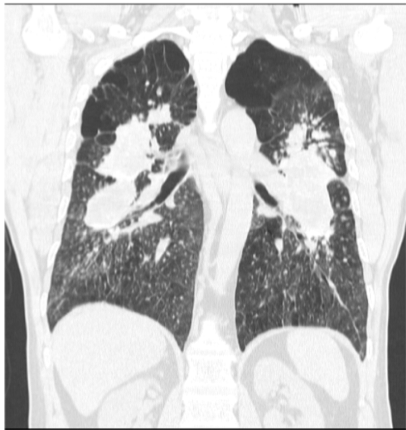

This shows diffuse pulmonary metastases, which _____ DPLD

This shows diffuse pulmonary metastases, which are not DPLD